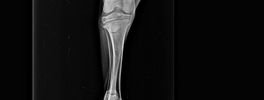

Images

Digital X-Ray